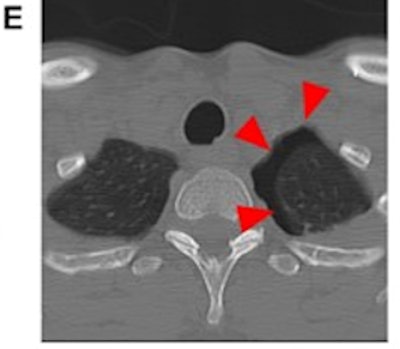

Most conditions related to intimate partner violence are fractures in the face (48.3%), fingers (9.9%), or upper trunk (9.8%), and it can be easy to interpret them as routine trauma, according to the authors. That's why radiologists should thoroughly review the medical history of cases that are suspicious for domestic abuse, discuss these cases with the referring physician, and conduct a private conversation with the patient, educating them on available resources for victims, the authors wrote.